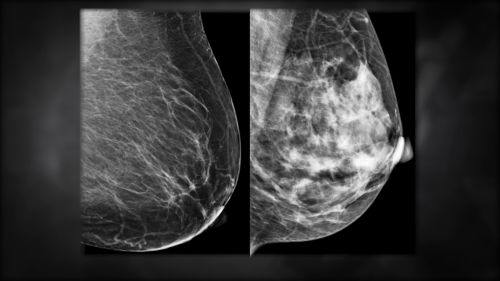

Así, el director de ese hospital, Eduardo Pujol, detalló: “Actualmente, el hospital registra en promedio, 1.000 cirugías por año, 10.000 radiografías, 2.500 tomografías y 400 mamografías”.